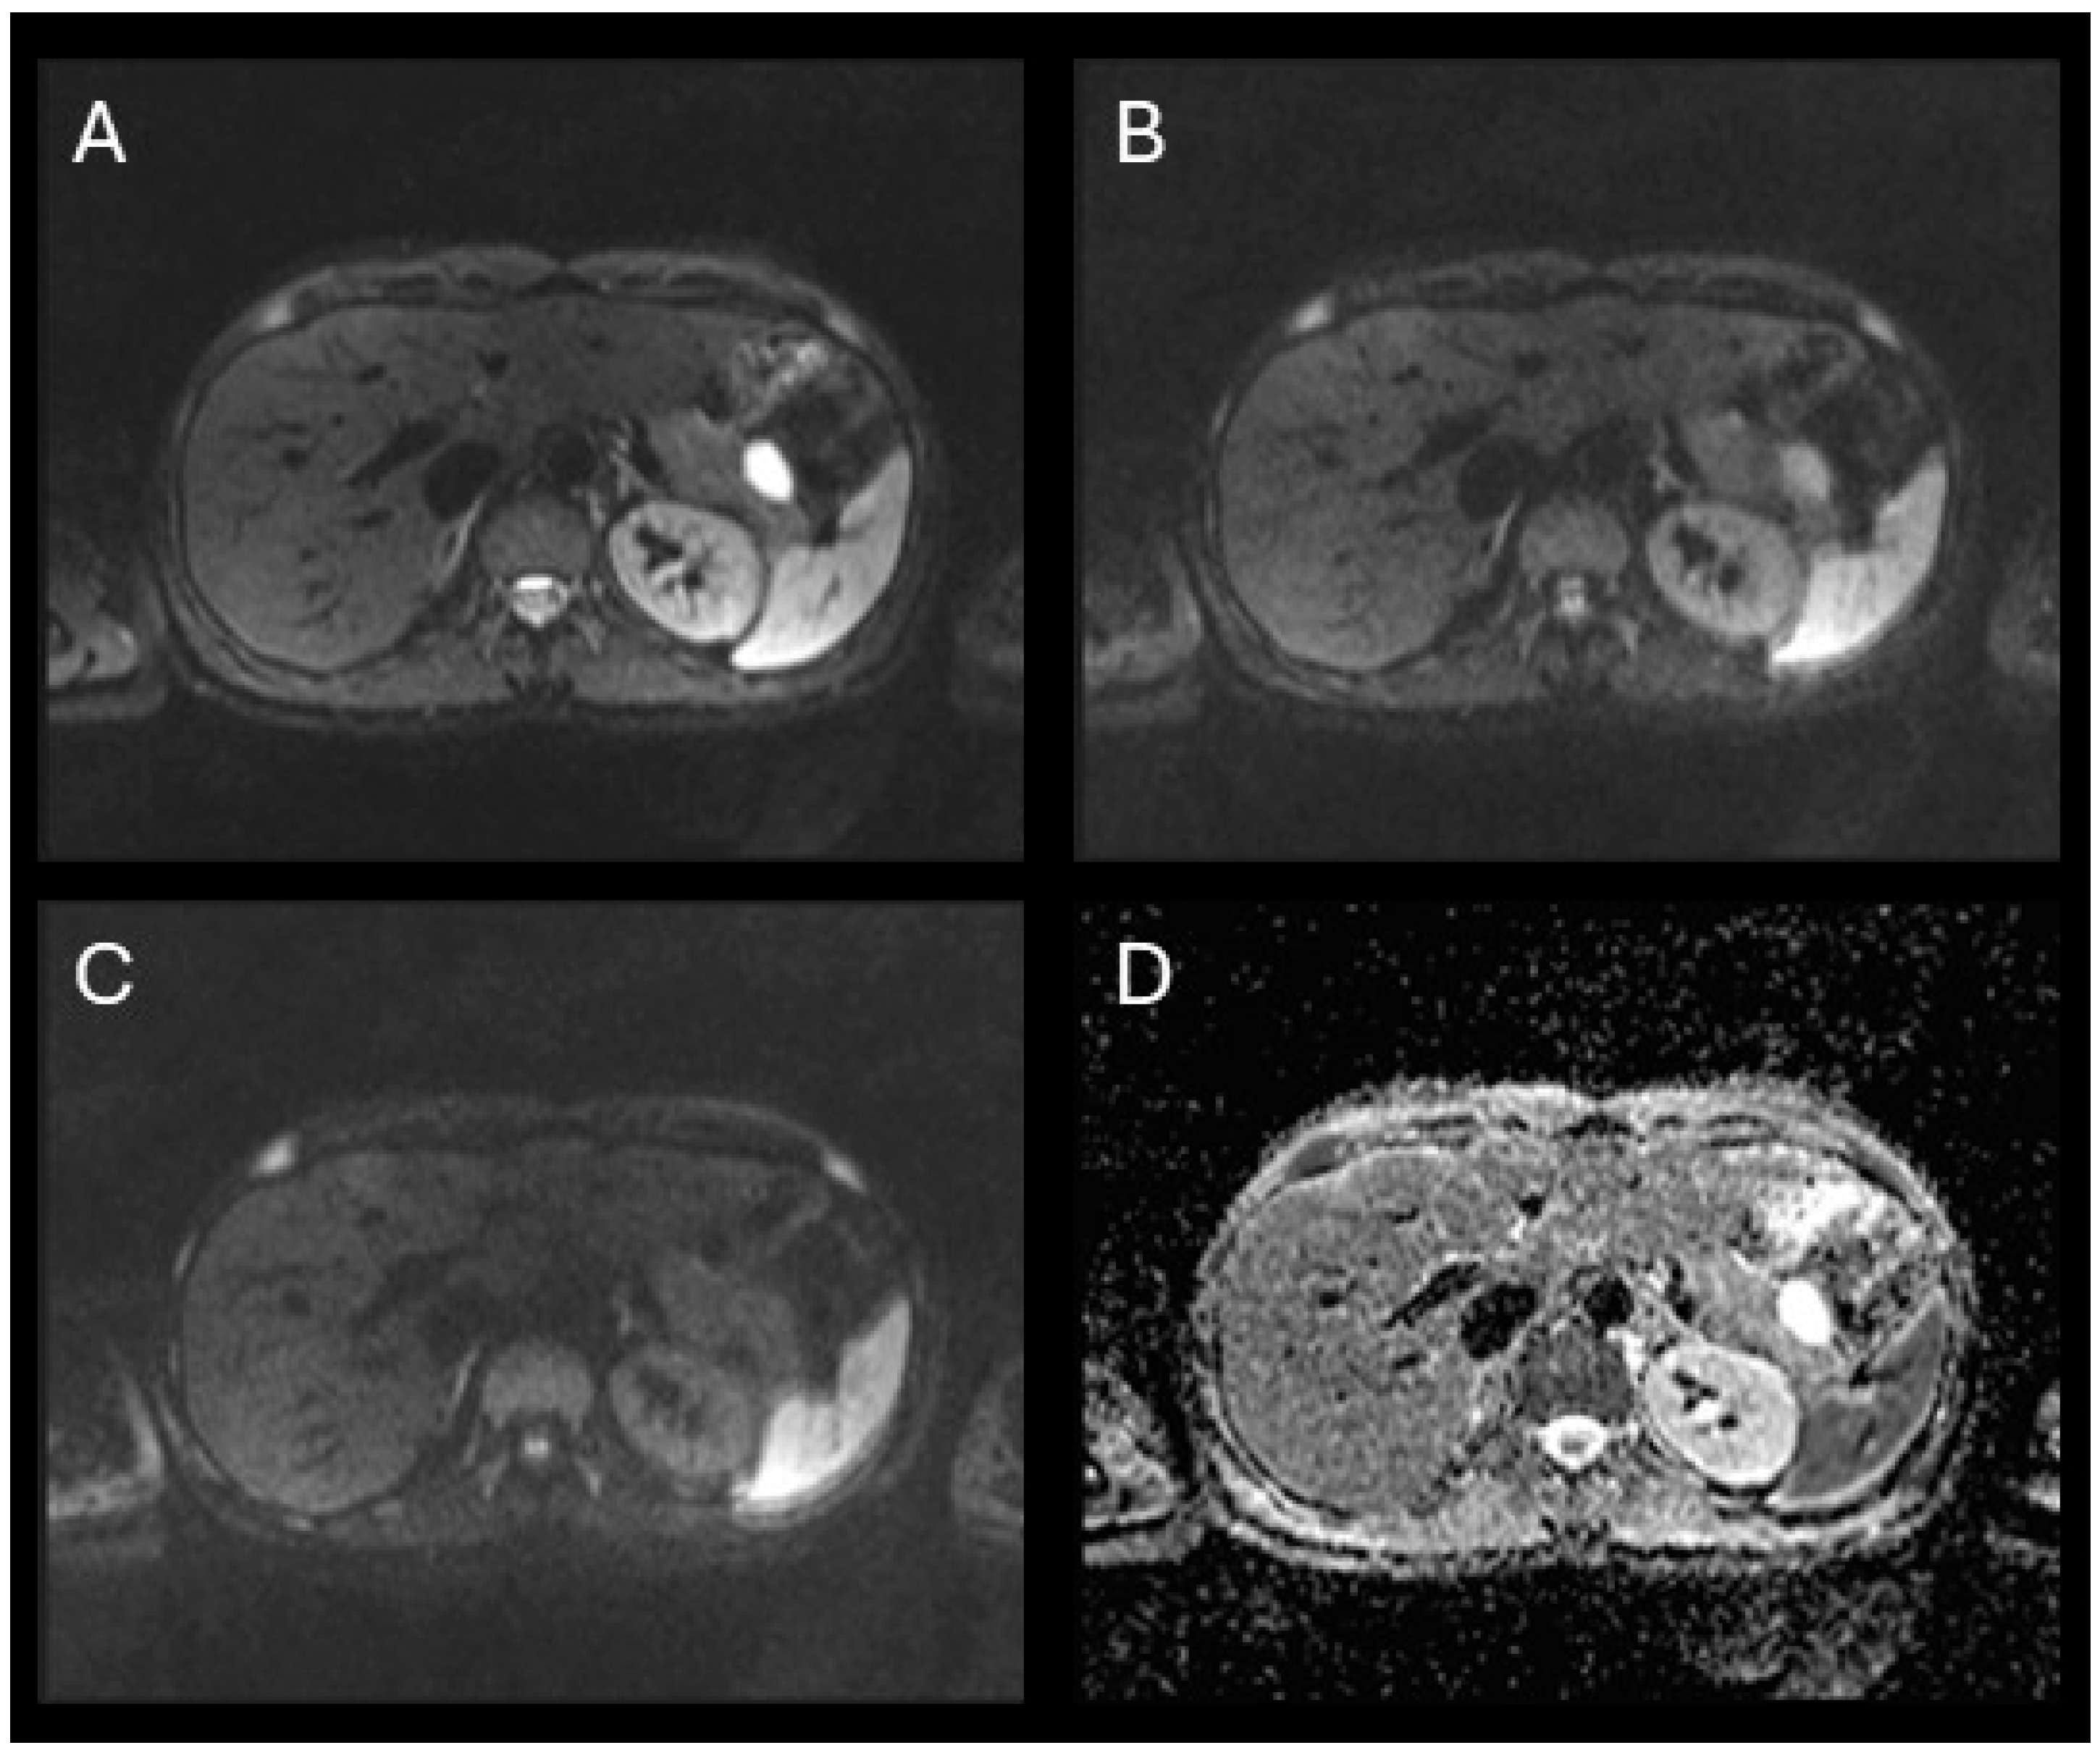

Background: Pancreatic hamartoma (PH) is an exceptionally rare, benign, mass-forming lesion accounting for less than 1% of all pancreatic tumors. Its rarity and non-neoplastic nature contribute to significant diagnostic challenges, often leading to misclassification as malignant disease. This study presents a case of PH and a systematic review of all reported cases, with emphasis on histopathological and imaging characteristics. Methods: A comprehensive electronic search of PubMed, Scopus, and Web of Science was conducted up to 1 April 2025, to identify eligible case reports and series. Results: We describe a 37-year-old woman with a cystic lesion of the pancreatic tail, ultimately confirmed histologically as a cystic pancreatic hamartoma following distal pancreatectomy with splenectomy, with an uneventful postoperative course. Of 687 screened studies, 51 met the inclusion criteria, comprising 77 cases (68 adults, 9 pediatric). PHs occurred most frequently in males (52.9%), with a mean age of 59.5 ± 12.9 years, and were often asymptomatic (57.4%). The pancreatic head was the most common site (52.9%). On MRI, PHs typically exhibited low T1-weighted and high T2-weighted signal intensity, with no FDG uptake (82%) and moderate or no restriction on DWI, distinguishing them from neuroendocrine tumors (NETs). Histologically, most lesions were solid (64.7%) or solid–cystic (35.3%), with low spindle cell cellularity and absent Langerhans islets. Conclusions: Low T1WI signal and moderate DWI signal are the key features distinguishing PHs from NETs. Incorporating these findings with EUS-FNA and immunohistochemistry can support a provisional diagnosis and help avoid unnecessary radical surgery.